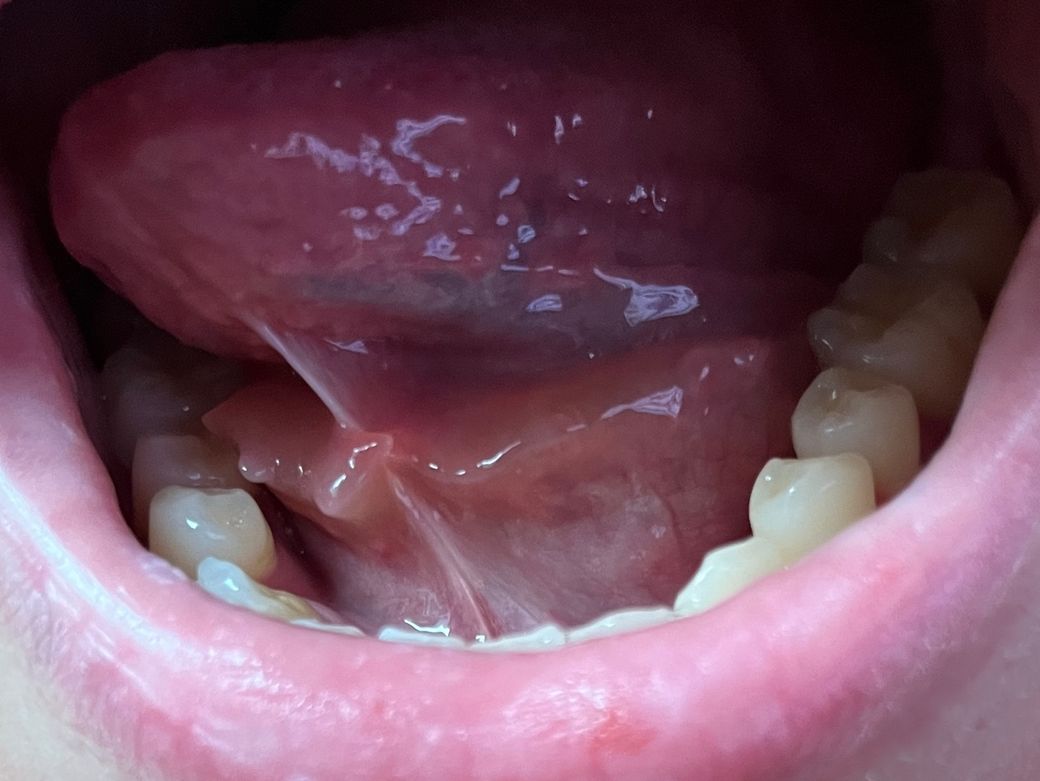

더불어 해당 증상이 수개월에 한 번꼴로 나타나다 보니 하룻밤 자고 일어나면 가라앉아있거나 호전되어 심각성을 느끼지 못했었는데 올해 초부터 아래 사진처럼 혀 아래에 침샘 주머니(?)가 돌출되고 침 넘김 시, 이물감이 느껴지며 불편합니다.

• 1번 째 사진